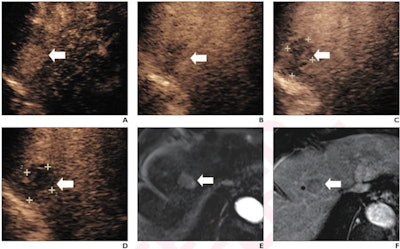

(A) Arterial-phase CEUS image shows a 25-mm segment-8 lesion with non-rim hyperenhancement (arrow). (B) CEUS image in portal-venous phase shows corresponding early washout (arrow). (C) CEUS image in late phase shows corresponding late and mild washout (arrow). (D) CEUS image in Kupffer phase shows marked Kupffer defect (arrow). The patient, a 71-year-old woman, also underwent evaluation by dynamic contrast-enhanced MRI using gadoxetate disodium. (E) Axial arterial-phase image shows 23-mm segment-8 lesion with non-rim arterial phase hyperenhancement (arrow). (F) Axial portal-venous phase image shows corresponding non-peripheral washout (arrow). This observation was classified as LR-M by modified CEUS criteria using perfluorobutane, and as LR-5 by CT/MRI LI-RADS v2018. The pathologic diagnosis based on surgical resection was intrahepatic cholangiocarcinoma. Images courtesy of ARRS.The LR-5 category on CEUS shows "very high" specificity but has lower sensitivity than CT/MRI. But perfluorobutane microbubbles for CEUS have a particular phase called Kupffer that enhances liver parenchyma -- an effect not seen when CEUS is performed using conventional contrast agents, the group noted. They suggested that these Kupffer-phase findings could improve sensitivity in the LR-5 category.